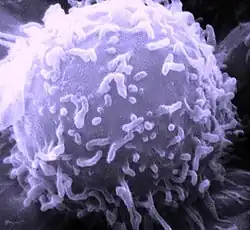

- T-lymfocyt

- B-lymfocyt

- NK buňka